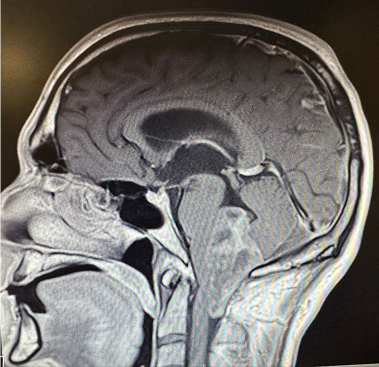

Excellence in Neurosurgery

& Vascular Care

Dr. Ziad A. Hage is a board-certified neurosurgeon specializing in cerebrovascular and endovascular neurosurgery, as well as skull base surgery. With years of experience and cutting-edge expertise, he is committed to providing exceptional patient outcomes.